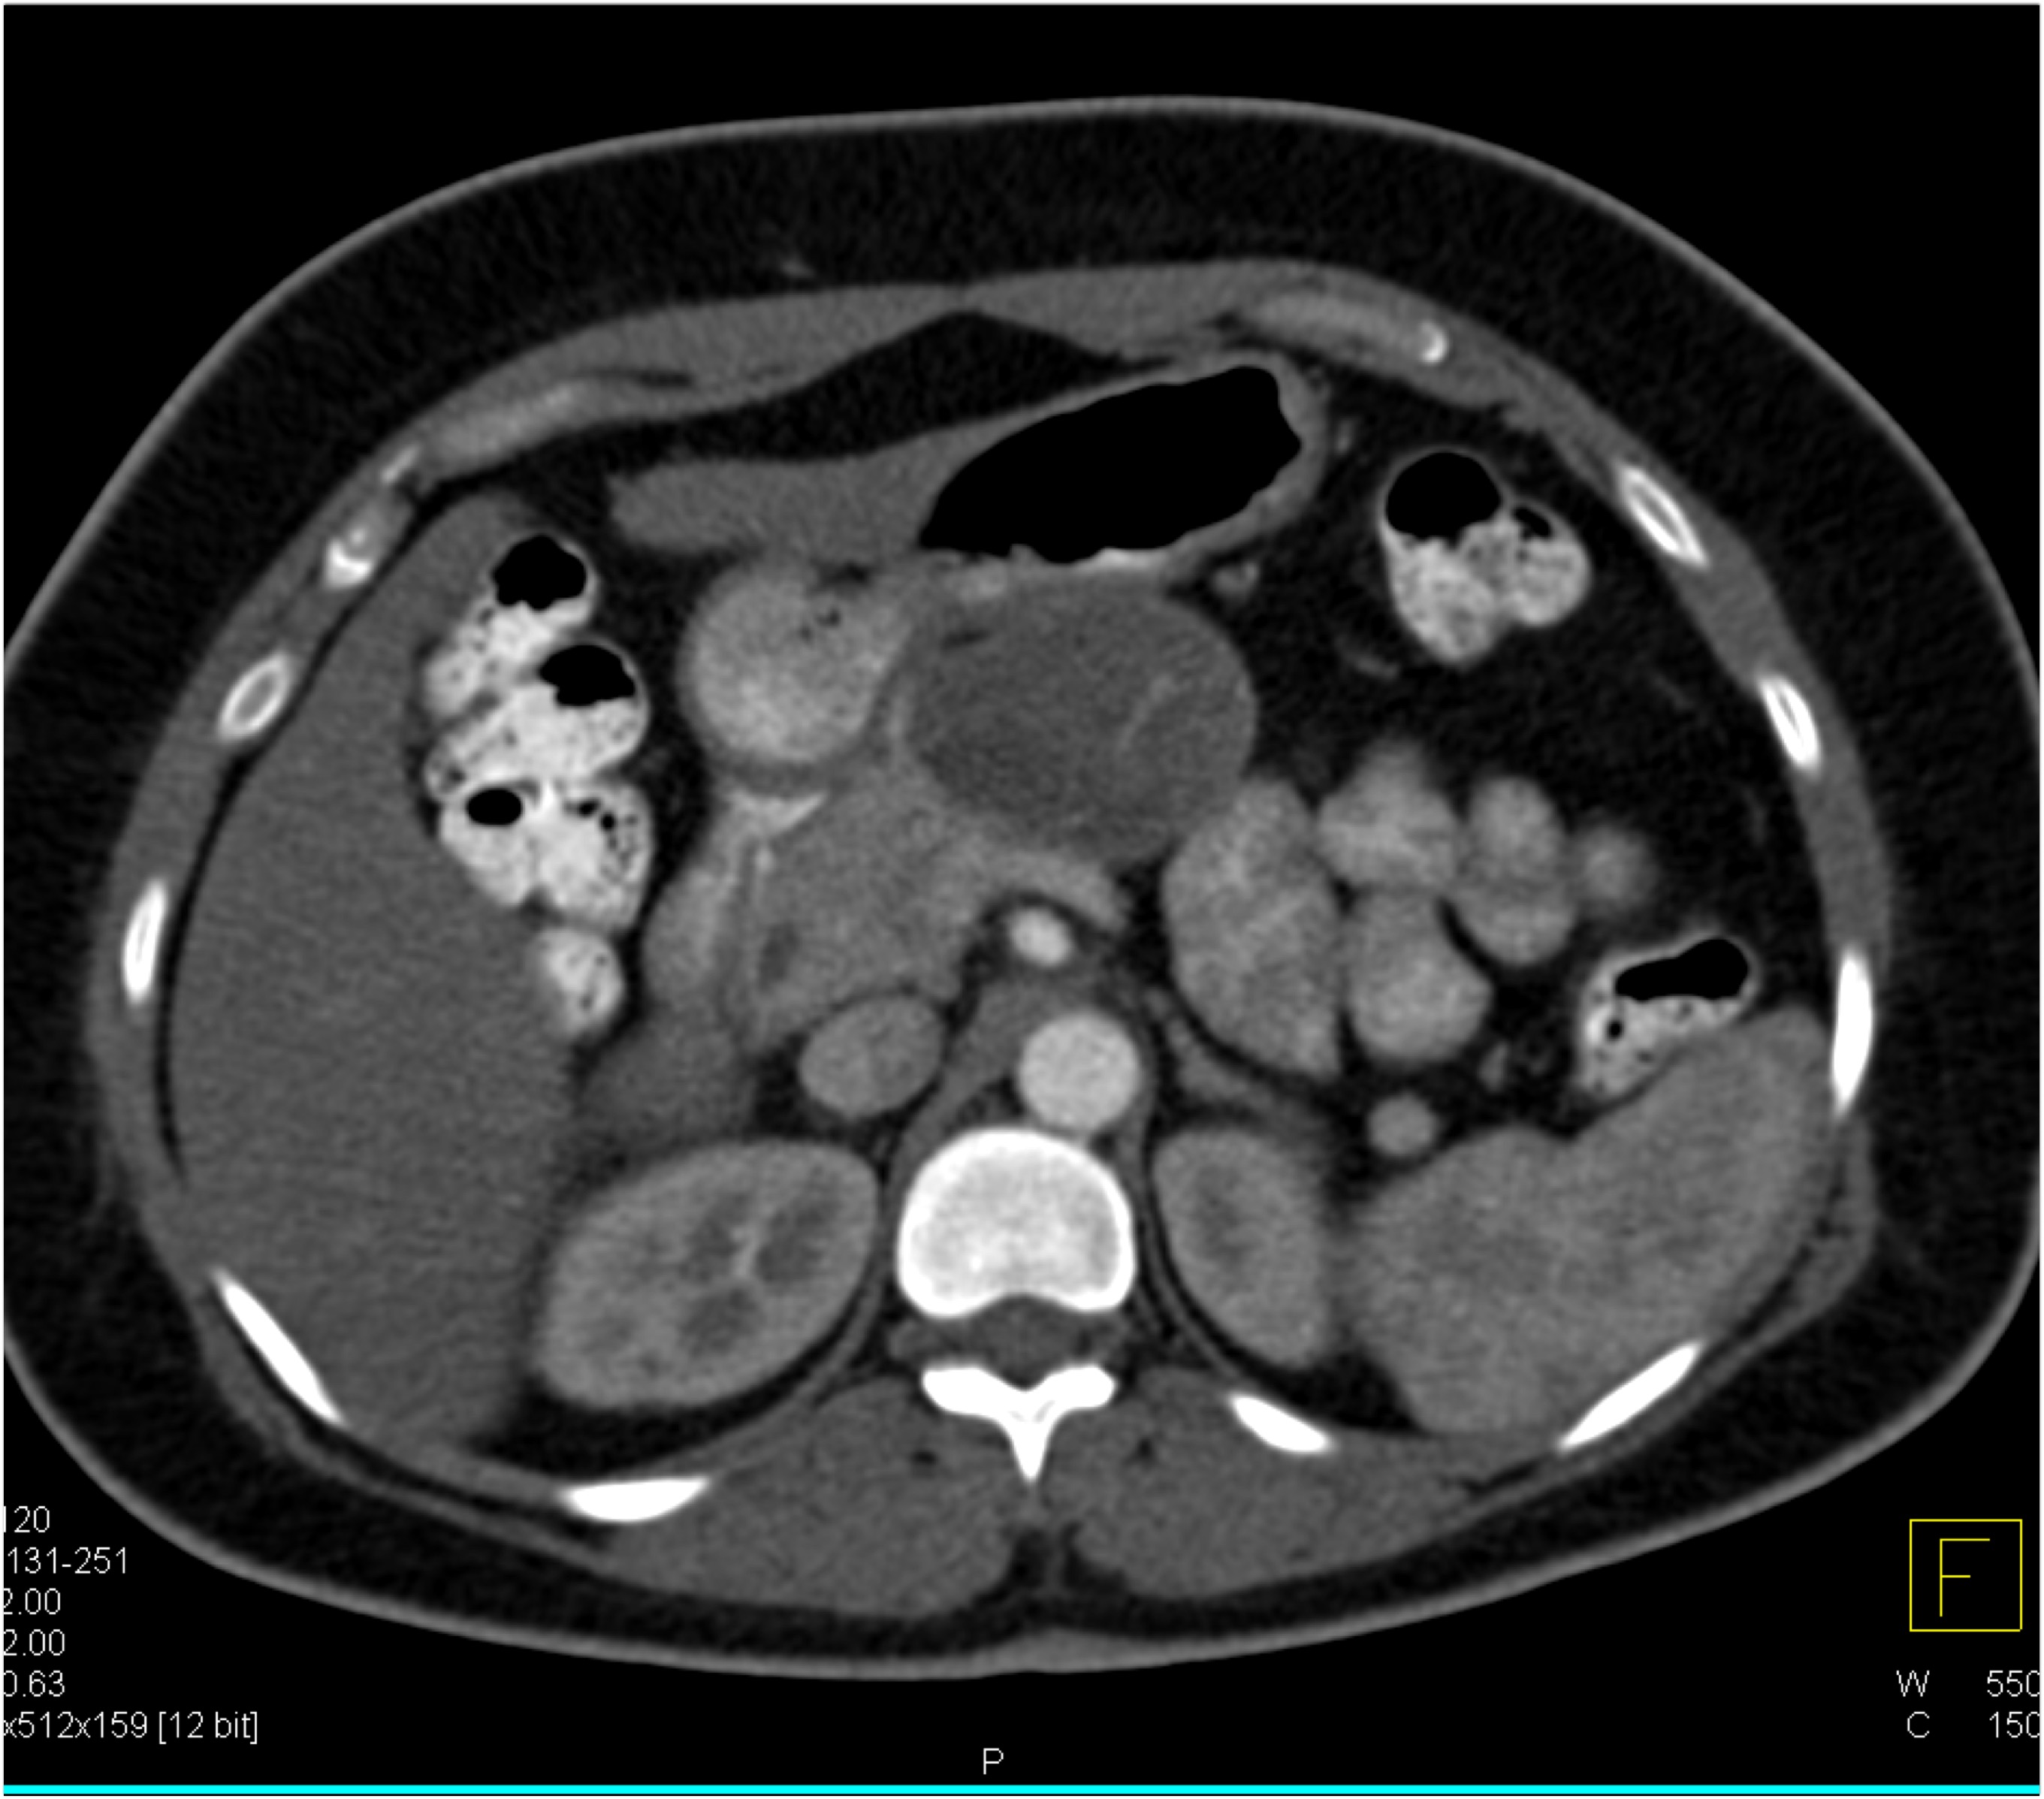

1) The best diagnosis in this patient with RLQ pain and fever is?

salmonella infection

acute appendicitis

Crohn’s disease

TB of the ileum